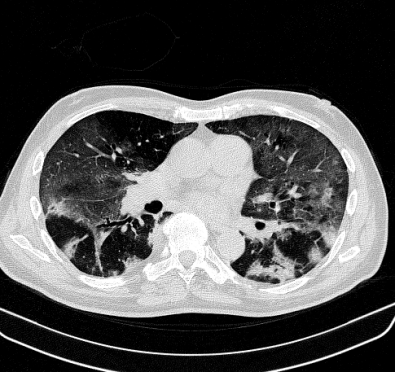

Lung segmentation results for the polymorphic and nonpolymorphic models are shown in Figure 3. Quantitative evaluation of lung segmentations was performed on CT images by comparing the segmentations to ground truth manual segmentations. The Dice coefficient was used to measure volume overlap and the average symmetric surface distance (ASSD) was used to assess boundary accuracy. The ASSD and Dice coefficient results for each of the four evaluation datasets are shown in Table 2. Overall, on the COVID-19 dataset the polymorphic model achieved an average ASSD of mm and average Dice coefficient of . By comparison, the nonpolymorphic model achieved an average ASSD of mm and average Dice coefficient of . ASSD and Dice coefficient results with respect to nonaerated lung volume fraction are displayed in Figure 4. Two-way analysis of variance revealed a significant interaction between model and nonaerated fraction for each evaluation metric, indicating that the regression coefficients with respect to nonaerated fraction were significantly different for polymorphic vs. nonpolymorphic models.

Lobar segmentation results for the proposed method and PTK are shown in Figure 5 for right lungs and Figure 6 for left lungs. For each image in the COVID-19 dataset (133 images in total), the lobar segmentation result was used to extract the amount of poor aeration () and consolidation () in each lobe. Common phenotypes of COVID-19 affected lungs were identified by hierarchical clustering over the fraction of poorly aerated and consolidated tissue in each lobe. Dendrographic analysis in Figure 7 reveals four primary clusters of patients that were identified by the hierarchical clustering: (a) mild loss of aeration primarily in the two lower lobes without consolidation; (b) moderate loss of aeration focused in the two lower lobes with or without consolidation in lower lobes; (c) severe loss of aeration throughout all lobes with or without consolidation; and (d) severe loss of aeration and consolidation throughout all lobes.